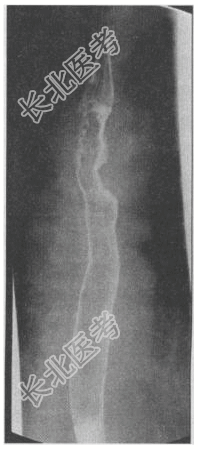

- [材料题] 患者女,63岁。主诉:进行性吞咽困难半年余。上消化道造影如图所示。

- 简答题1、本病例最可能的诊断是?

- 简答题2、食管癌的影像特征有哪些?